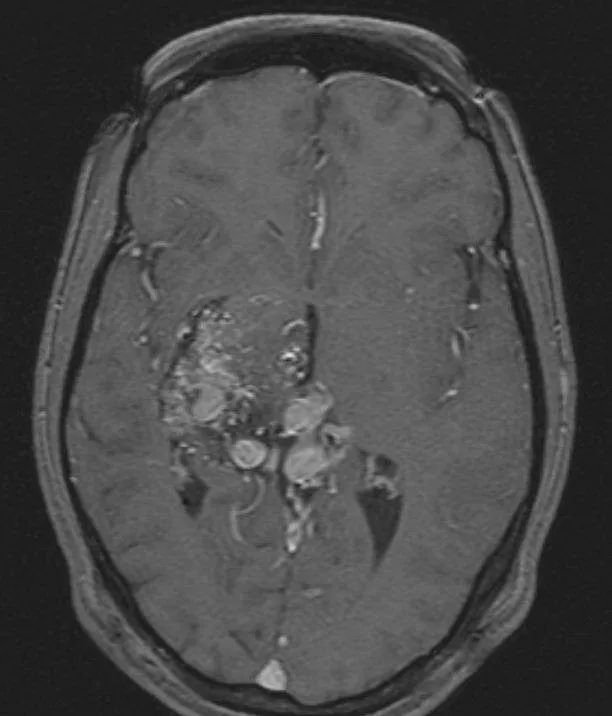

▼轴位T1加权像,既往行γ刀治疗

然而,就在伽马刀治疗 3 年后,造影显示AVM大部分闭塞,颞叶内侧少量残留畸形团向 BVR 引流。如果想要解决颞叶内侧依然活跃的动静脉畸形,手术是Amanda的更优选择。